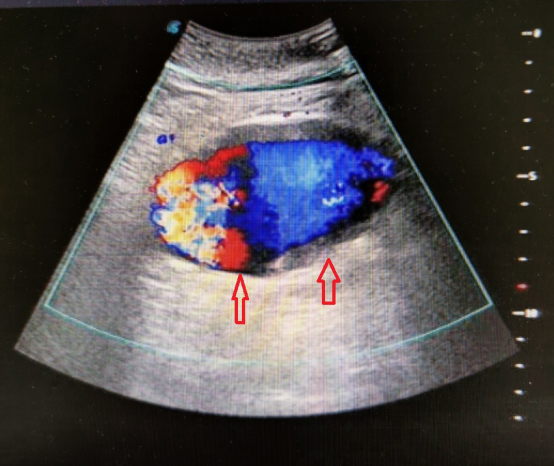

是腹主动脉瘤伴什么?

图片尺寸768x576